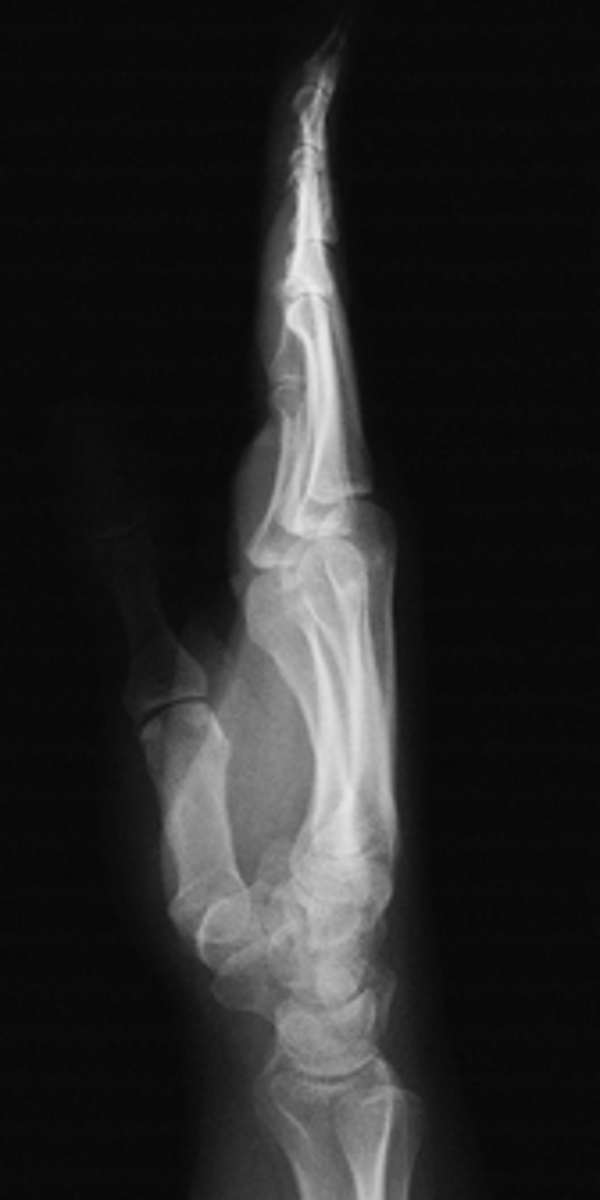

Lateral Thumb